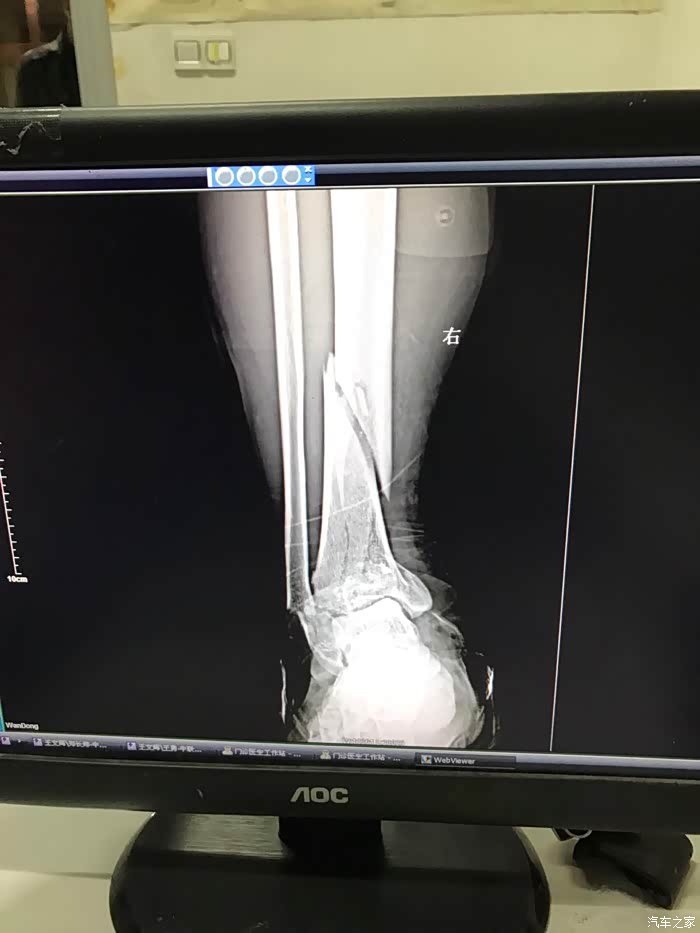

记得当时撞车后,我发现右脚像秤砣一样乱晃,我就明白了,厉害了我的哥。

此时还没有水肿,正在处理伤口看腿型大家可以看得出畸形了。